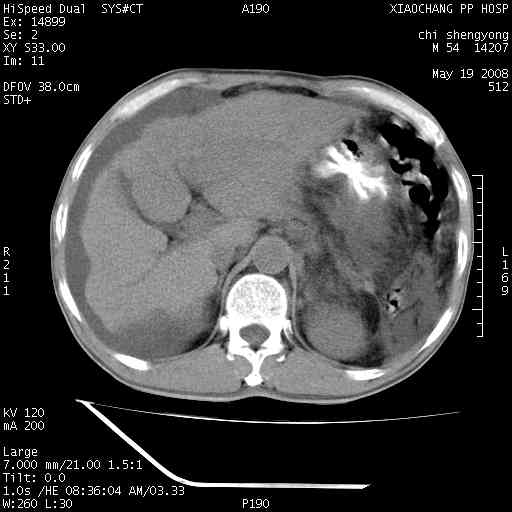

以下是引用zjzjr在2008-5-21 10:52:00的发言:[br]肝左叶巨块型肝癌伴门静脉左支瘤栓形成.肝硬化、腹水,胃底静脉曲张,脾术后改变。

以下是引用随光逐影在2008-5-21 16:20:00的发言:[br]1)肝左叶肝癌伴门静脉左支瘤栓形成,腹膜后淋巴结转移。2)肝硬化、腹水、胃底静脉曲张。3)胆囊炎。4)脾脏缺如,为切除术后所致。